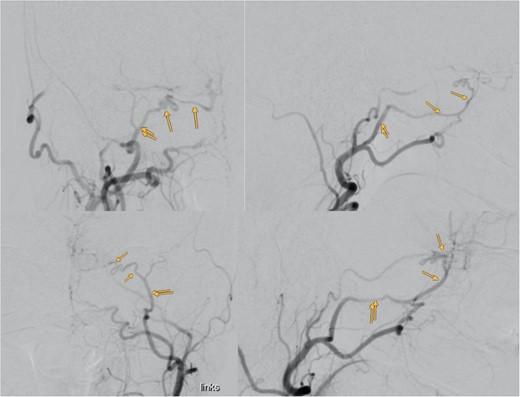

Despite normal blood hormonal status except for low cortisone levels, the patient’s confusion improved upon initiation of physiological and pharmacological cortisone replacement therapy. Digital subtraction angiography revealed that the meningioma was predominantly supplied by bilateral sphenopalatine arteries and bilateral anterior cerebral arteries, with anastomosis through the COF (Fig. 3).

Showing the digital subtraction angiography of the left external carotid artery in four perspectives: posteroanterior view (upper left), lateral view (upper right), posteroanterior view (lower left), and lateral view (lower right). Additionally, the figure shows the middle meningeal artery and the anastomosis, which are marked.

Our case’s angiography revealed the meningioma’s vascular supply from bilateral sphenopalatine arteries and bilateral anterior cerebral arteries, with anastomosis through COF (Fig. 3). Catheterizing the ECA with such anastomosis poses challenges, especially near the ophthalmic artery. Caution during procedures, proper catheter positioning, and gentle injection techniques are crucial for safe embolization [4].